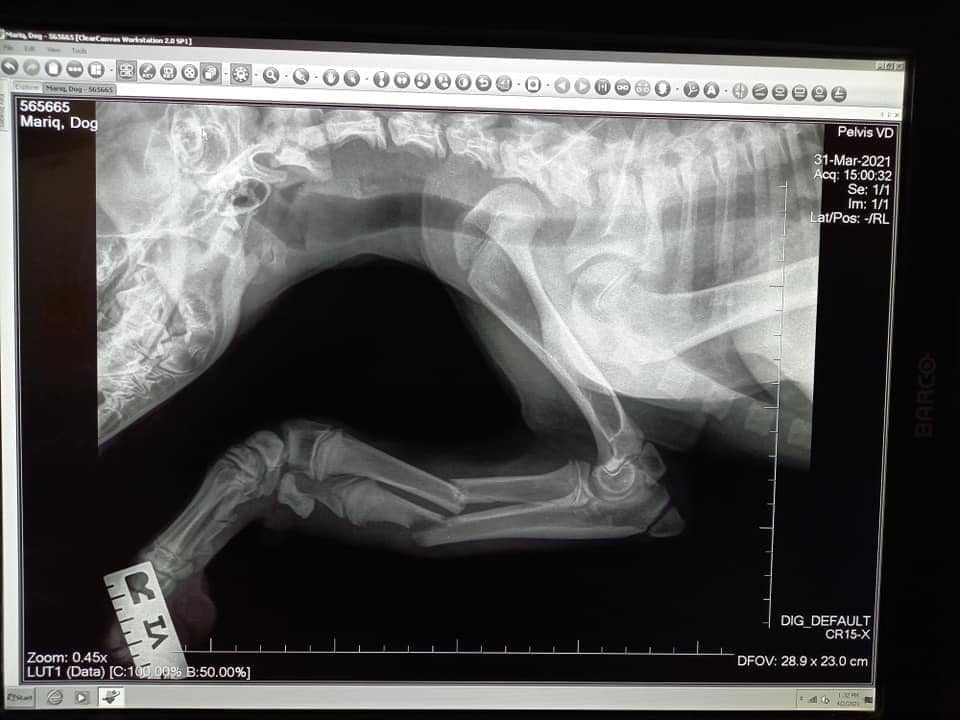

Auch dieser Fall lässt nur erahnen, welche Qualen der Vierbeiner erlitten haben muss: Maria ist ca. 3-4 Monate alt und hatte vier gebrochene Beine. Laut Tierarzt womöglich von mehreren Verkehrsunfällen. Die Kleine muss unglaubliche Schmerzen gehabt haben und konnte nicht mehr laufen. Zum Glück haben Nina & Nuriye Maria gefunden! Laut Tierarzt kann Maria ein normales Leben führen, wenn sie an allen Beinen operiert wird. Dies ist inzwischen für die Hinterläufe und einen Vorderlauf geschehen, morgen wird das letzte Bein operiert. Maria hat die bisherigen OPs gut weggesteckt und wir sind zuversichtlich, dass auch morgen alles gut gehen wird. Die Zuckermaus hat es so verdient, auf allen vier Pfoten das Leben zu erkunden! Aber auch in Bulgarien kosten Operationen etwas und deshalb bitten wir um Unterstützung für Maria.